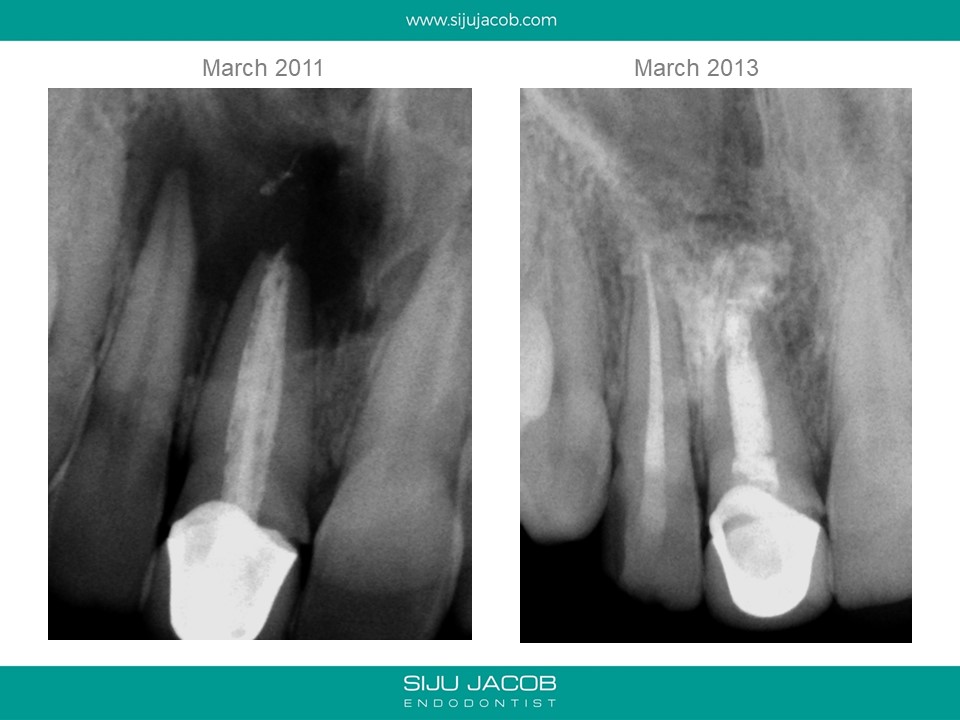

This patient presented with a large lesion associated with a previously endo treated central Incisor with a open apex. The adjacent lateral tested non-vital. I did Endo on the lateral incisor. In the central, I decided to pack Calcium hydroxide till the lesion shrank in size before obturating with MTA. The plan was to keep the original crown in place till there was some evidence of bone fill. The patient disappeared for two years and came back with the lesion completely healed and a solid barrier formed apically through Apexification. I obturated with Gutta percha (No MTA needed) and Advised new crown